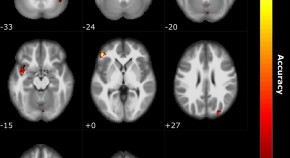

• Measures of neural processing can be obtained non-invasively from all areas of the human brain but one, the olfactory bulb. Here, the authors show that signals obtained from EEG electrodes at the nasal bridge represent responses from the human olfactory bulb, the so-called Electrobulbogram.